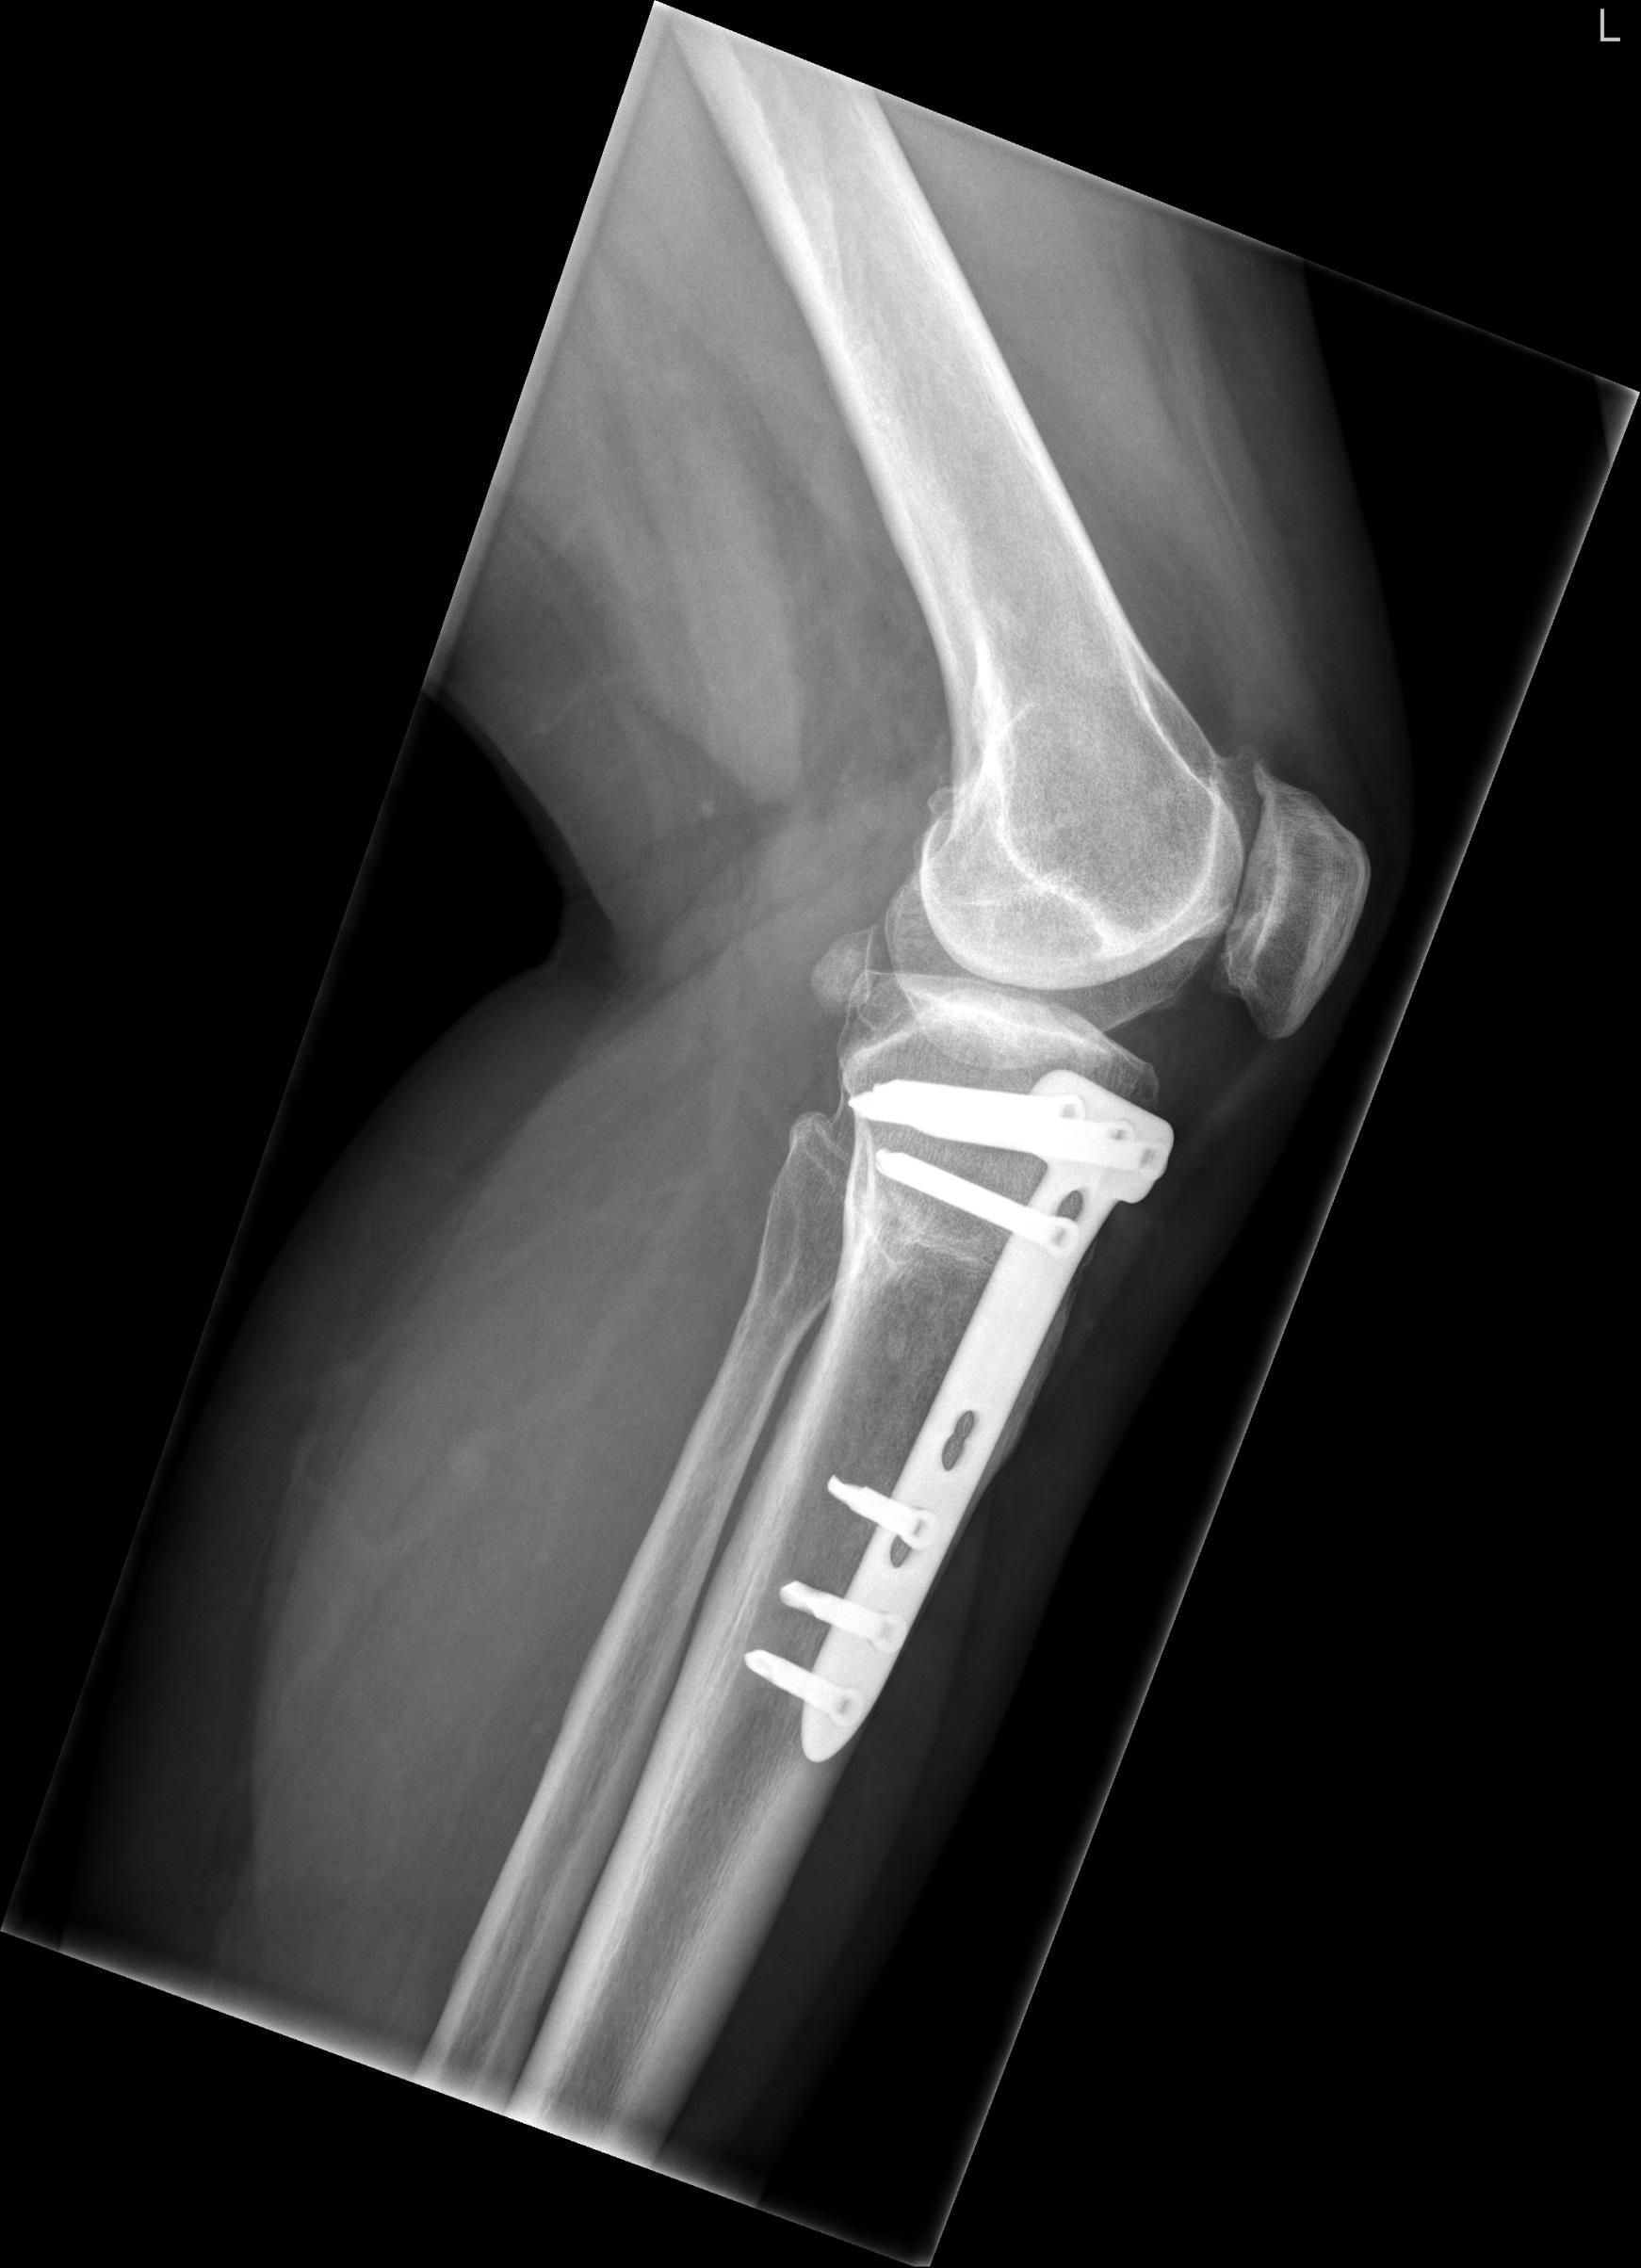

Intervention After administrating analgesics, a reduction was performed by hyperflexing the knee, unlocking the superior patellar osteophyte from the trochlear groove (figure 4.) After two weeks of weight bearing in an extension splint, the patient was advised to resume normal activities. After reduction of the patellar dislocation the X-ray showed an ISR of 0.74. The X-ray also showed a suprapatellar osteophyte.

Comparison Guidelines are lacking, concerning which surgical technique to use for HTO. The latest Cochrane update in 2014 concluded that there is no evidence for selecting a most favourable osteotomy technique.1 Currently, the preferred technique is the medial OWHTO popularised by Lobenhofer in 2003.2,3 The main disadvantage of OWHTO is a change in patellar height.4 Patella infera is a common result after OWHTO with a proximal tuberosity osteotomy (figure 5). Otsuki et al stated that for every 1° correction the Caton-Deschamps index is decreased by 1.7%.5 This unfavourable outcome of OWHTO is well recognised in literature.6 To prevent patella infera Gaasbeek et al. introduced a novel technique of a biplanar osteotomy leaving the tibial tubercle attached to the proximal segment; the distal tuberosity osteotomy in OWHTO7 (figure 6). It resulted in an unchanged patellar height postoperatively.

Outcome At five months follow-up the patient did not have a new inferior patellar dislocation. She was back to her previous level of activities. The insecurities and concerns following the dislocation were diminishing. Relevant literature Inferior patellar dislocation is a rare finding only described in case reports. Two types can be found.8 The first, mostly in adolescent males, occurs after a direct blow to the flexed knee, which forces the superior pole of the patella into the notch. The quadriceps tendon is partially peeled off the anterior patellar surface. It can be treated non-operatively with a closed reduction and immobilisation of the limb in extension. The second type of inferior patellar dislocation is the degenerate type. It is caused by a hyperflexion injury in the presence of marginal patellar osteophytes. In contrast to the adolescent type, the extensor mechanism remains firmly attached. Unlocking is performed by flexing the knee. Surgical exploration is unnecessary. Early mobilisation is recommended. Patella infera is considered to be present when de ISR is <0.8.4 Patella infera is a common finding after medial OWHTO. In this case postoperatively a decrease of the ISR from 0.89 to 0.83 was measured. However, at six years follow-up it had progressively decreased to an ISR of 0.74. This late effect of surgery is only hypothetically addressed in the literature. It is possibly caused by contracture of the patellar ligament due to arthrofibrosis or scarring in this region. Excessive new bone formation during healing of the osteotomy might cause contracture of the patellar tendon.4 We believe the infrapatellar fat pad of Hoffa is also of importance in the late onset patella infera. Injury to this fat pad by direct damage or secondary to hematoma formation from a proximal tuberosity osteotomy might lead to late onset patella infera. The measurements in this report are possibly erroneous due to the X-ray at the final follow-up not being a perfect lateral view, and by interobserver variability. Advice Our case can be classified as a degenerate type of inferior patellar dislocation. The combination of the patella infera and a suprapatellar osteophyte created the circumstances for the inferior patellar dislocation to occur. We think the patella infera is introduced both direct postoperative and late onset, caused by the OWHTO with proximal tuberosity osteotomy. Therefore, we would like to use this case report to advocate the use of the distal tuberosity osteotomy in OWHTO. This technique should be taken into special consideration when the patient, who is planned for a HTO, has a low ISR, is planned for a large correction of >10° and/or has a suprapatellar osteophyte.7 In case of patella alta and/or patellar instability an OWHTO with proximal tuberosity osteotomy is recommended. By decreasing the ISR the patellar height can either be normalised or the patella can be stabilised in these cases. Acknowledgements Dr. R.D.A. Gaasbeek, orthopaedic surgeon. Disclosure statement None of the authors have anything to disclose.